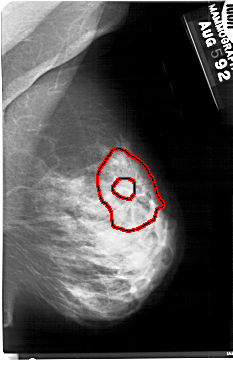

A_1693_1.RIGHT_MLO

FILE: A_1693_1.RIGHT_MLO.OVERLAY

TOTAL_ABNORMALITIES 1

ABNORMALITY 1

LESION_TYPE CALCIFICATION TYPE PLEOMORPHIC DISTRIBUTION CLUSTERED

LESION_TYPE MASS SHAPE IRREGULAR MARGINS SPICULATED

ASSESSMENT 5

SUBTLETY 4

PATHOLOGY MALIGNANT

TOTAL_OUTLINES 2

BOUNDARY

CORE